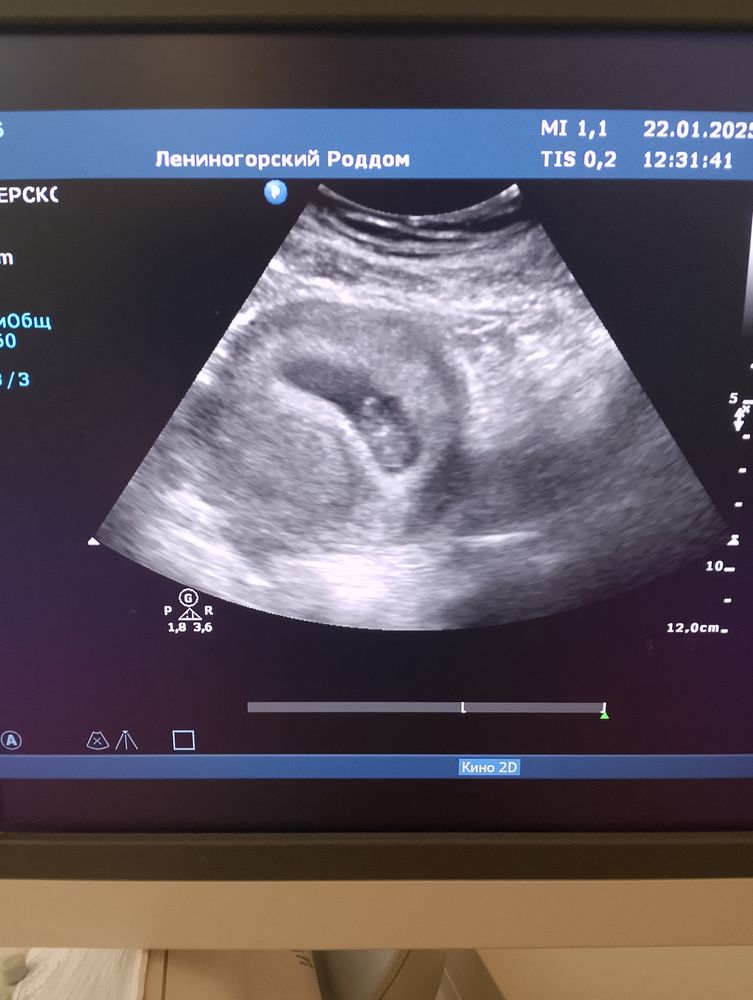

Амина Костюк, здравствуйте да сделали врач предположила что это был второй которые не развился

Вероника Шевцова, а при повторном УЗИ второго черного кружочка уже не было ?

Вероника Шевцова, скорее всего как я и думала не развился второй просто. Такое часто бывает. Но если учесть все риски многоплодной это и лучше возможно .

Вероника Шевцова, по этому фото я бы не сказала что двойня , на снимке виду одно большое чёрное пятно , в нём эмбрион и желточный мешочек . И второе чёрное маленькое круглое , но оно же прям очень маленькое в сравнении с другим ... Поэтому не думаю что двойня